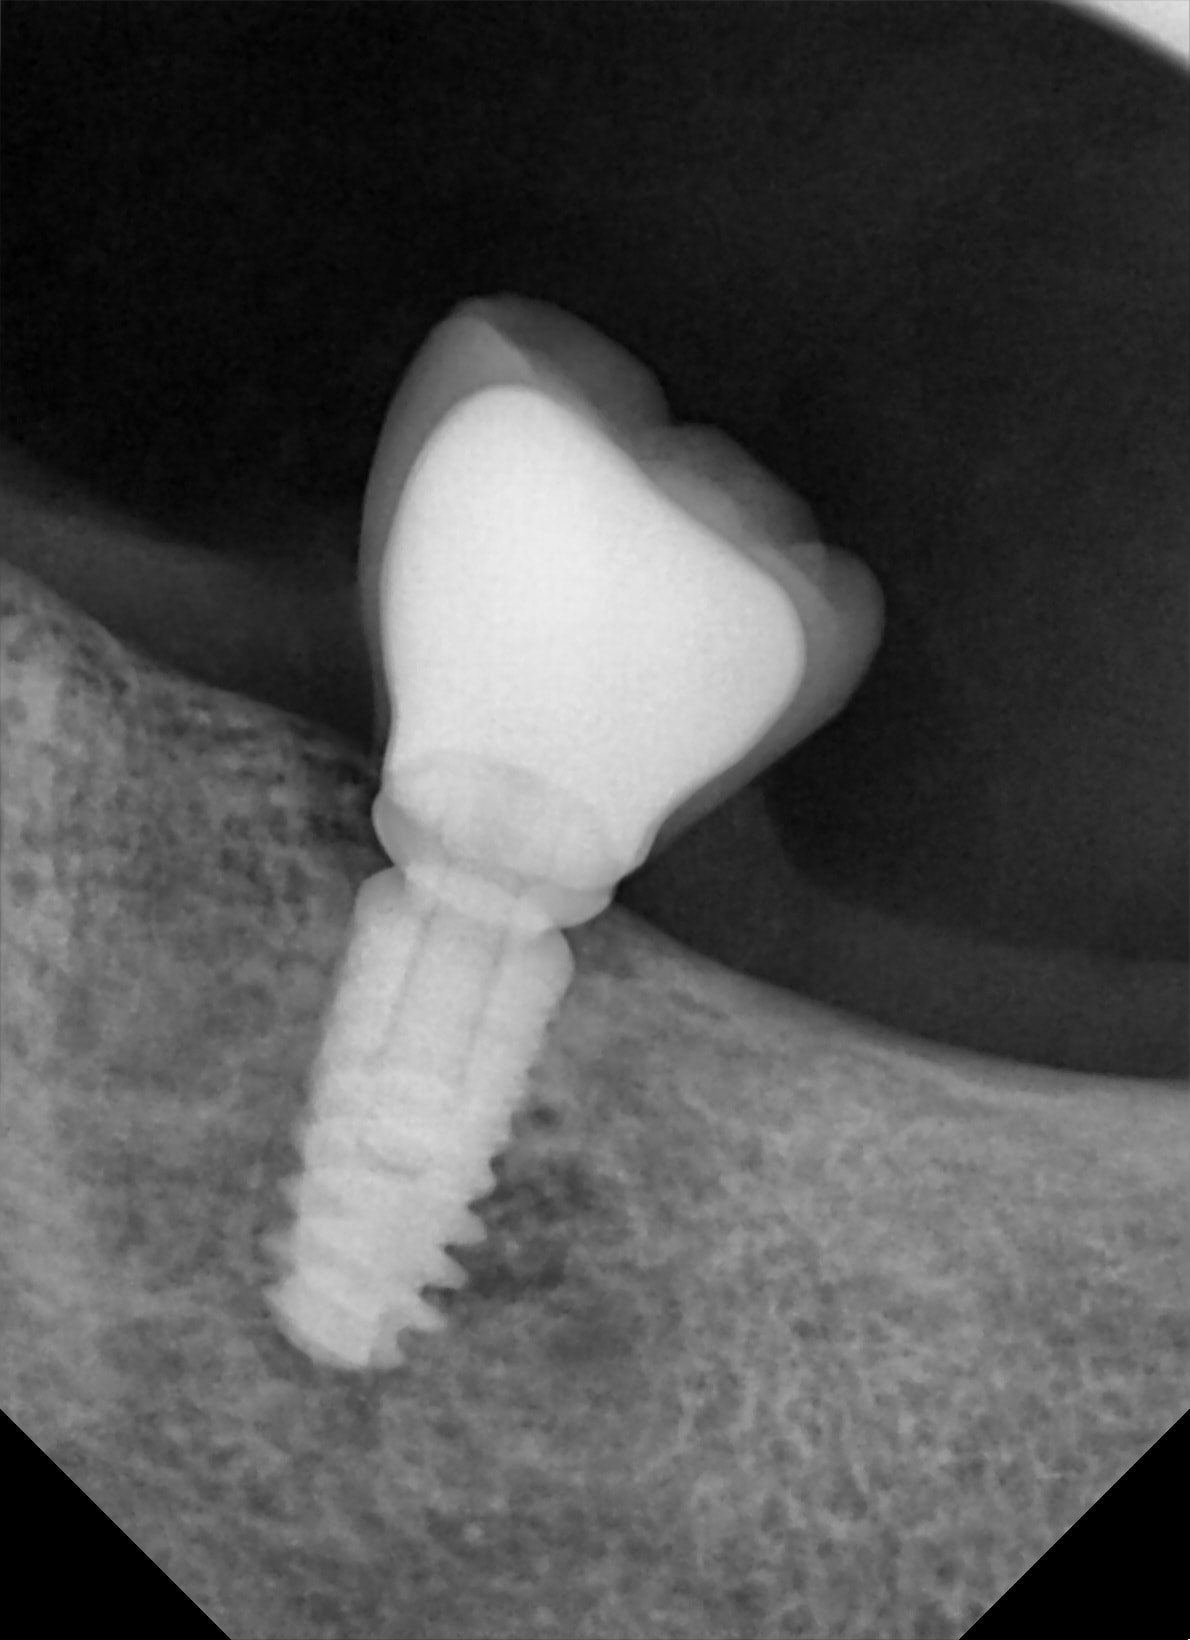

Bonjour, je ne connais pas les implants posés sur ce patient il y a plusieurs années sauf l'implant 35 qui est un zimmer. Le praticien est a la retraite et pas de moyen de savoir ce qu'il posait... Ce qui m’intéresse surtout c'est l'implant 37 pour faire un éventuel bridge 35-37.

rétroalvéolaire pour être sûr à 100% stp...

mais çà a une bonne gueule d'Ankylos....

ouaip, c'est bien de l'ankylos...